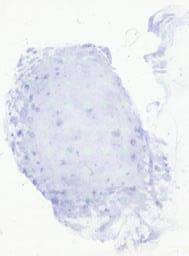

临床资料: 男,54岁,发现颈部两处肿物1年。双侧颈部局部探查:局部皮下软组织结构层次清晰,右侧颈部内可见一大小约24×8mm的淋巴结样回声,边界清,内回声不均匀血流信号,上述部位未见明显异常血流信号距体表约5mm。左侧颈部内可见数个淋巴结样回声,边界清,内回声不均匀,其中一个大小约6×5mm。CDFI:上述光团内及周边未见明感检查结果:双侧颈部软组织层异常占位(考虑淋巴结增大)。